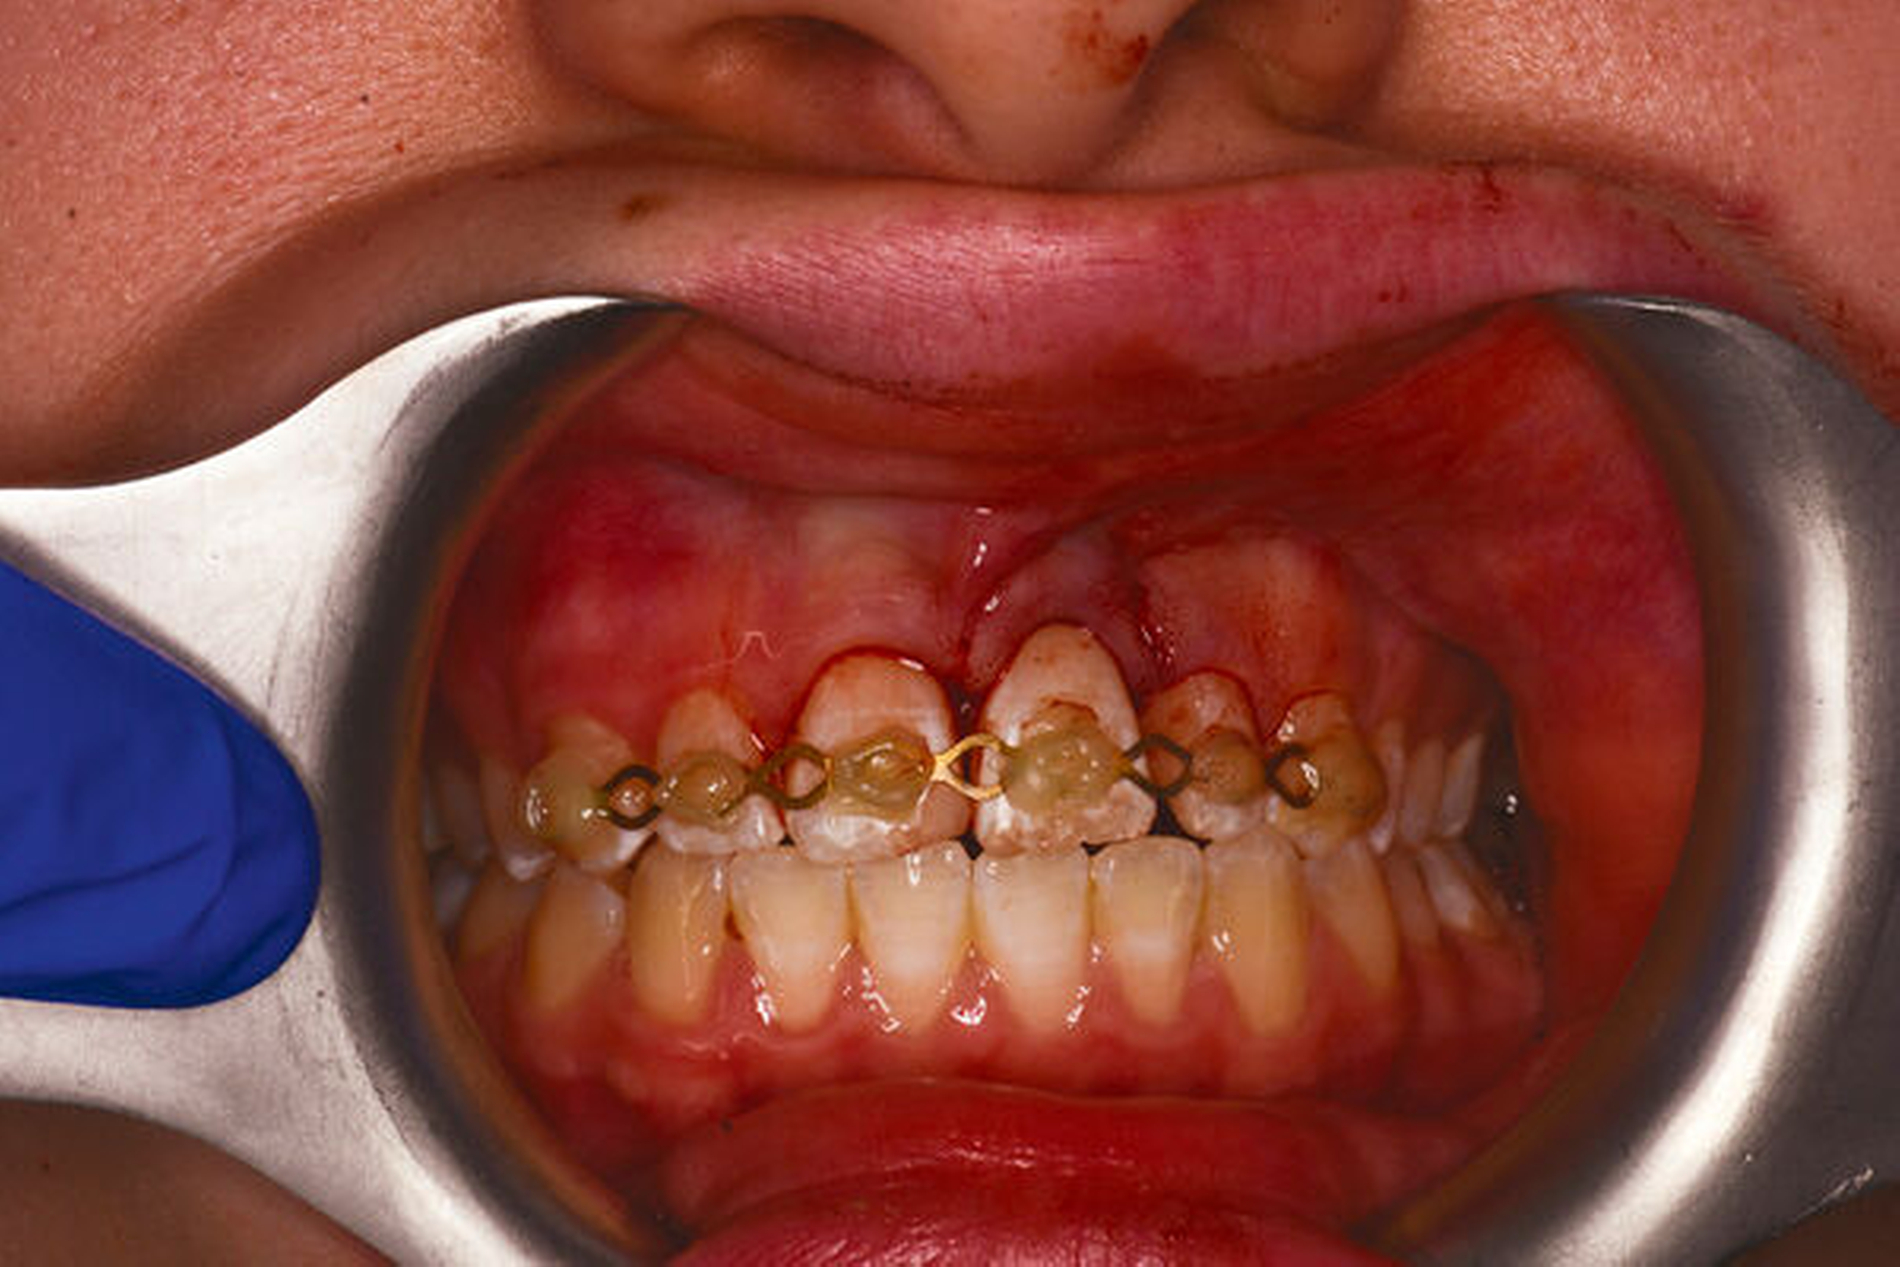

„Ubi pus, ibi evacua!“ – der lateinische Aphorismus wird häufig in vielen Bereichen der Medizin zitiert. Dieser Grundsatz trifft auch auf die Behandlung von akuten apikalen Abszessen zu. Der erste Weg der Behandlung sollte hier, wann immer möglich, über den Wurzelkanal gehen, um eine Drainage für den Pusabfluss zu schaffen (Abbildungen 1 und 2). Das nekrotische Pulpagewebe oder die bereits vorhandene Wurzelkanalfüllung gilt es von orthograd zu entfernen. Die Wurzelkanalpräparation kann die Drainage des Abszesses weiter unterstützen. Mittels der chemischen Desinfektion im Zuge eines suffizienten Spülprotokolls erfolgt eine weitere Elimination von Mikroorganismen und nekrotischem Pulpagewebe aus dem Wurzelkanallumen. Zur weiteren Desinfektion und zur Anhebung des pH-Wertes wird eine wässrige Kalziumhydroxideinlage in den Wurzelkanal eingebracht. Ein „Offenlassen“ des Zahnes nach der Schmerzbehandlung gilt es zu vermeiden, da sich Mikroorganismen aus der Mundhöhle im Wurzelkanal ansiedeln und nachfolgend zu einem Biofilm kolonialisieren können [Siren et al., 1997]. Lässt sich der Pusabfluss aus dem Wurzelkanal nicht stoppen, kann ein Zahn in Ausnahmefällen für maximal 24 Stunden offengelassen, am folgenden Tag in der Praxis endodontisch versorgt und mit einem provisorischen Verschluss versehen werden [Schäfer et al., 2021].

Symptomatische irreversible Pulpitis (Abbildung 3)